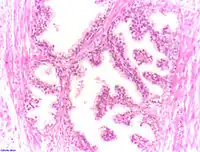

Histologie

Le diagnostic est obtenu par des biopsies prostatiques multiples, réalisées de manière échoguidée et par voie transrectale. Elle permet également de réaliser le score de Gleason, de grande valeur pronostique.

.jpg) Adénocarcinome prostatique

Adénocarcinome prostatique.jpg) Adénocarcinome prostatique

Adénocarcinome prostatique- Adénocarcinome ; tissus indifférenciés

- Invasion périneurale par un adénocarcinome prostatique. HE, x400

Anatomopathologie

Le cancer entreprend la portion périphérique de la glande, au contraire de l'hypertrophie prostatique bénigne qui intéresse la zone centrale, périurétrale.

Score de Gleason

La structure tissulaire des cancers de la prostate varie des formes différenciées (cellules cancéreuses ressemblant aux cellules saines), dite de grade 1, aux formes les moins différenciées (cellules cancéreuses présentant beaucoup de caractères atypiques par rapport aux cellules saines), dite de grade 5.

Plusieurs grades peuvent se rencontrer au sein d'un même tissu. Le score de Gleason est calculé de la façon suivante : on additionne les deux grades les plus représentés de la tumeur. Le premier chiffre représentant le score du contingent le plus représenté. Ainsi 4+3 est plus péjoratif que 3+4

Si la somme est de 6 ou moins, le cancer est dit bien différencié, donc de meilleur pronostic ; 7 : le cancer est moyennement différencié ; 8 ou plus : le cancer est peu différencié, donc de moins bon pronostic.